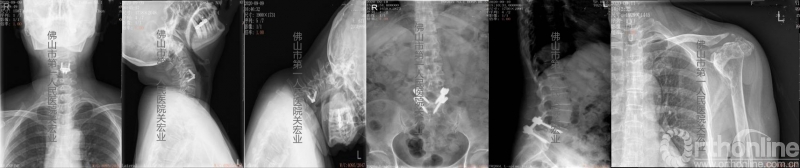

影像学检查:

术前放射检查

术前CT

术前MR

诊断:

1.类风湿性关节炎

2.寰枢椎半脱位

3.颈椎术后

4.腰椎滑脱术后

5.左足、左肩类风湿性改变

6.糖尿病